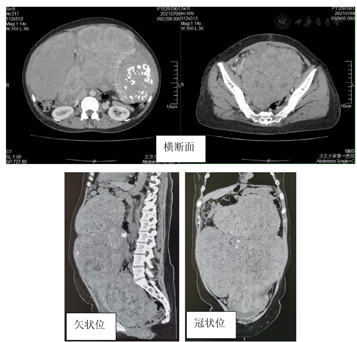

CT:巨大混杂密度站位,分叶状,表面可见血管走形,病灶分布于大网膜、肠系膜内,腹腔脏器及全部小肠呈推挤样向外移位,子宫及膀胱向前推移,下腔静脉显示不清,远端静脉回流受阻,盆腔可见少量积液。纵膈受压,部分肺膨胀不全。未见淋巴结肿大(图3、图4)。

影像学提示巨大实性肿物充满盆腹腔,呈混合密度,表面见血管。纵膈受压,部分肺膨胀不全,腹腔脏器被推挤向外移位,下腔静脉远端回流受阻,子宫、膀胱及直肠明显受压。穿刺活检病理报告子宫平滑肌瘤。